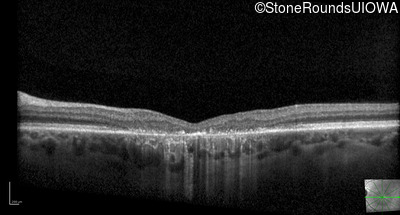

Optical Coherence Tomography - Left - 20/200

Exemplar / OCT Stack